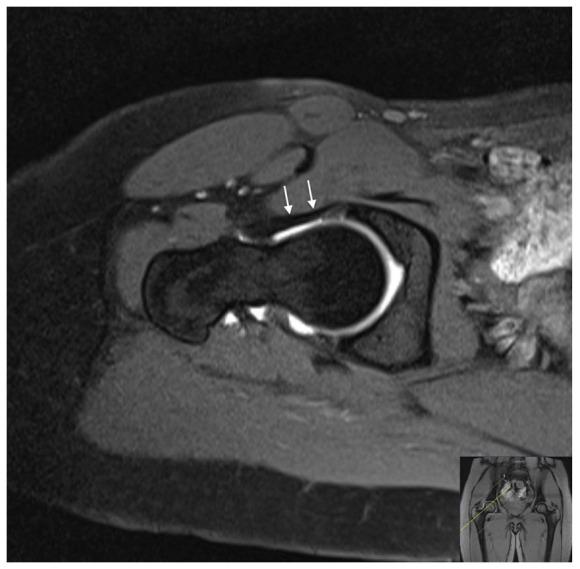

The purpose of this systematic literature review is to analyse the role of the iliofemoral ligament (ILFL) as a hip joint stabilizer in the current literature.A total of 26 articles were included in the review. The ILFL is the largest hip ligament consisting of two distinct arms and is highly variable, both in its location and overall size, and plays a primary role in hip stability; in the case of hip dislocation, the iliofemoral ligament tear does not heal, resulting in a persistent anterior capsule defect. Clinically, the ILFL is felt to limit external rotation in flexion and both internal and external rotation in extension.The abduction-hyperextension-external rotation (AB-HEER) test is overall the most accurate test to detect ILFL lesions. Injuries of the ILFL could be iatrogenic or a consequence of traumatic hip instability, and can be accurately studied with magnetic resonance imaging. Different arthroscopic and open techniques have been described in order to preserve the ILFL during surgery and, in case of lesions, several procedures with good to excellent results have been reported in the existing literature.The current systematic review, focusing only on the ILFL of the hip, summarizes the existing knowledge on anatomy, imaging and function and contributes to the further understanding of the ILFL, confirming its key role in anterior hip stability. Future studies will have to develop clinical tests to evaluate the functionality and stability of the ILFL. Cite this article: 2021;6:545-555. DOI: 10.1302/2058-5241.6.200112.

本系统文献综述的目的是分析在当前文献中髂股韧带(ILFL)作为髋关节稳定器的作用。本综述共纳入26篇文章。髂股韧带是最大的髋关节韧带,由两个不同的臂组成,其位置和整体大小变化很大,在髋关节稳定性中起主要作用;在髋关节脱位的情况下,髂股韧带撕裂不会愈合,导致前囊持续缺损。临床上,感觉髂股韧带在屈曲时限制外旋,在伸展时限制内旋和外旋。外展-过伸-外旋(AB-HEER)试验总体上是检测髂股韧带损伤最准确的试验。髂股韧带损伤可能是医源性的,也可能是创伤性髋关节不稳定的结果,磁共振成像可以准确地研究这种损伤。为了在手术中保留髂股韧带,已经描述了不同的关节镜和开放技术,并且在现有文献中报道了几种效果良好至极佳的手术方法。当前的系统综述仅关注髋关节的髂股韧带,总结了关于其解剖、成像和功能的现有知识,有助于进一步了解髂股韧带,证实其在髋关节前侧稳定性中的关键作用。未来的研究将不得不开发临床测试来评估髂股韧带的功能和稳定性。引用本文:2021;6:545 - 555。DOI:10.1302/2058 - 5241.6.200112。